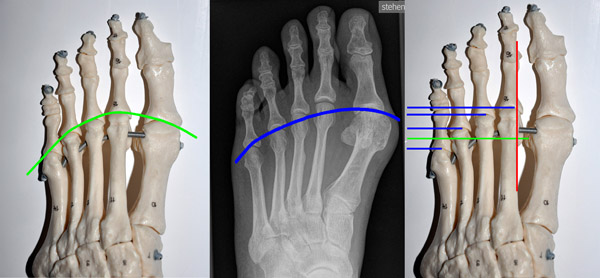

Die Indikationsstellung des geeigneten Operationsverfahrens erfolgt nach dem Schweregrad der Hallux valgus Deformität (Lehmann  DE, 2003). Diese kann anhand verschiedener Winkelparameter graduiert werden, nämlich dem Hallux valgus Winkel, dem Intermetatasale – I – Winkel sowie dem distalen Gelenkflächenwinkel, der häufig auch als PASA-Winkel bezeichnet wird (Abb. 1 – 4). Bedeutsam für die Wahl des geeigneten Vorgehens ist auch die Berücksichtigung der Kongruenzsituation der Gelenkpartner im Großzehengrundgelenk, der durch ein entsprechendes Weichteilrelease Rechung getragen werden muß. Nach der Korrektur soll ein harmonisches Vorfußalignement erreicht werden (Abb.5) (Maestro M, 1995, Ludloff  K,  1918, Pisani G, 1998).

Metatarsaleköpfchenparabel nach Maestro und Pisani

Abbildung 5

• Abbildung 5: Markus Walther